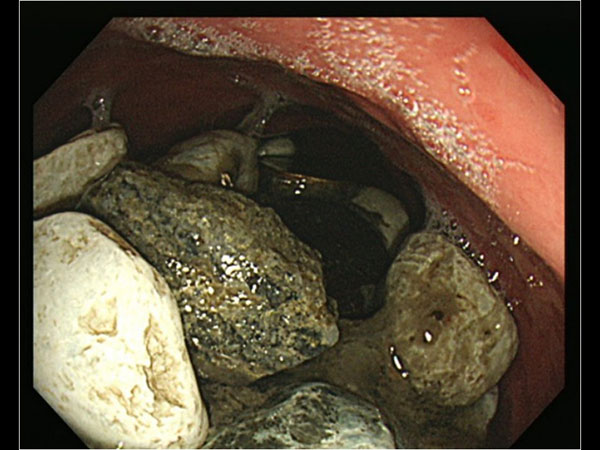

ಆಸ್ಪತ್ರೆಗೆ ಚಿಕಿತ್ಸೆಗೆಂದು ಬಂದ ವ್ಯಕ್ತಿಯ ಹೊಟ್ಟೆಯು ಉಬ್ಬರಗೊಂಡಿತ್ತು ಮತ್ತು ಹೊಟ್ಟೆಯನ್ನು ವೈದ್ಯರು ಮುಟ್ಟಿ ನೋಡಿದ ವೇಳೆ ಸಣ್ಣ ಸಣ್ಣ ಕಲ್ಲುಗಳು ಪತ್ತೆಯಾಗಿದೆ. ಮತ್ತಷ್ಟು ಪರಿಶೀಲನೆ ನಡೆಸಿದ ವೇಳೆ ವೈದ್ಯರಿಗೆ ಆಘಾತ ಉಂಟಾಯಿತು. ಯಾಕೆಂದರೆ ಆ ವ್ಯಕ್ತಿಯ ಹೊಟ್ಟೆಯೊಳಗಡೆ ಸಣ್ಣ ಸಣ್ಣ ಕಲ್ಲುಗಳು, ಬಾಟಲಿಯ ಮುಚ್ಚಳ ಇತ್ಯಾದಿಗಳು ಕಂಡುಬಂದವು. ಇದು ಸಂಪೂರ್ಣ ಹೊಟ್ಟೆಯನ್ನು ವ್ಯಾಪಿಸಿತ್ತು.

ತನ್ನ ಹೊಟ್ಟೆಯಲ್ಲಿದ್ದ ಕಲ್ಲುಗಳು, ಬಾಟಲಿ ಮುಚ್ಚಳ ಇತ್ಯಾದಿಗಳನ್ನು ಕಂಡು ವೈದ್ಯರು ಅಚ್ಚರಿಗೊಂಡರು. ಈ ಬಗ್ಗೆ ಆ ವ್ಯಕ್ತಿಯಲ್ಲಿ ಕೇಳಿದಾಗ, ತನಗೆ ಆತಂಕ ಉಂಟಾದ ವೇಳೆ ನಾನು ಶಾಂತವಾಗಲು ಔಷಧಿ ತೆಗೆದುಕೊಳ್ಳುತ್ತಾ ಇದ್ದೆ. ಇದರೊಂದಿಗೆ ನಾಣ್ಯ, ಮುಚ್ಚಳ ಮತ್ತು ಸಣ್ಣ ಸಣ್ಣ ಕಲ್ಲುಗಳನ್ನು ಕೂಡ ನುಂಗುತ್ತಲಿದ್ದೆ ಎಂದು ಹೇಳಿದ್ದಾನೆ.

ಈ ವ್ಯಕ್ತಿಯನ್ನು ತಕ್ಷಣವೇ ಶಸ್ತ್ರಚಿಕಿತ್ಸೆ ಮಾಡಲಾಯಿತು ಮತ್ತು ವೈದ್ಯರ ಪ್ರಕಾರ ಇದು ತುಂಬಾ ಕಠಿಣ ಶಸ್ತ್ರಚಿಕಿತ್ಸೆಯಾಗಿತ್ತು. ಯಾಕೆಂದರೆ ಇಂತಹ ಶಸ್ತ್ರಚಿಕಿತ್ಸೆಯು ತುಂಬಾ ಕಠಿಣವಾಗಿರುವುದು ಮತ್ತು ಗ್ಯಾಸ್ಟ್ರೋಸ್ಕೋಪಿ ಮೂಲಕವಾಗಿ ಇದನ್ನು ತೆಗೆಯಬೇಕಾಯಿತು. ಬಾಯಿಯ ಮೂಲಕವಾಗಿ ತುಂಬಾ ತೆಳುವಾದ ಟ್ಯೂಬ್ ನ್ನು ಹಾಕಲಾಯಿತು. ಇದರ ಬಳಿಕ ತುಂಬಾ ಭಿನ್ನವಾಗಿರುವಂತಹ ಶಸ್ತ್ರಚಿಕಿತ್ಸೆ ವಿಧಾನದ ಮೂಲಕ ಹೊಟ್ಟೆಯಲ್ಲಿ ಇದ್ದ ಕಲ್ಲುಗಳು ಹಾಗೂ ಇತರ ಸಾಮಗ್ರಿಗಳನ್ನು ಹೊರಗೆ ತೆಗೆಯಲಾಯಿತು.